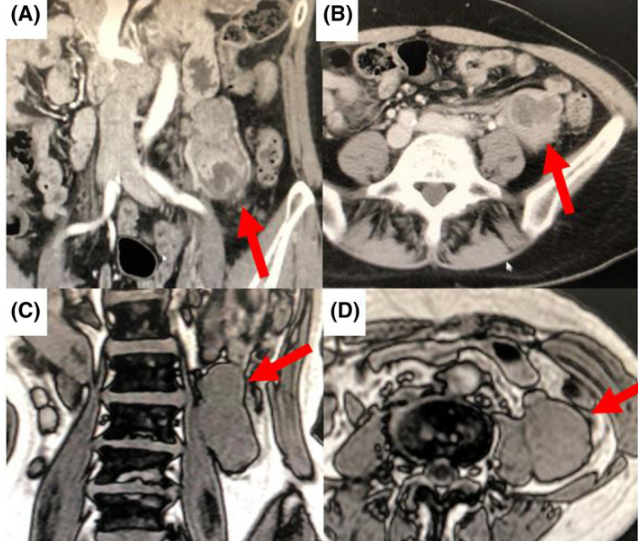

腹部增强CT提示左侧腹膜后或小肠系膜间一36*38*44mm椭圆形占位,质地均匀,表明光滑,肿块内可能存在坏死区或囊性退行性病变,仅术前影像学无法确定肿块位置,肿块距离大肠和小肠较远,肠道来源可能性小。磁共振(MRI)成像,T1加权图像显影欠佳,T2加权图像显影明显,如1A-D。

图1 A B腹部增强CT提示左侧腹膜后或小肠系膜间一36*38*44mm椭圆形占位;C-D磁共振(MRI)成像,T1加权图像显影欠佳,T2加权图像显影明显